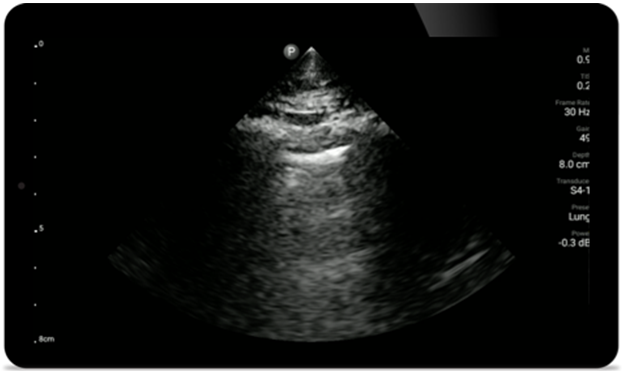

Use Lumify for airway and pulmonary assessment

Lumify POCUS solutions can help you detect the endotracheal tube within the trachea, assist in emergent cricothyrotomy procedures, diagnose pleural effusion and interstitial alveolar diseases.